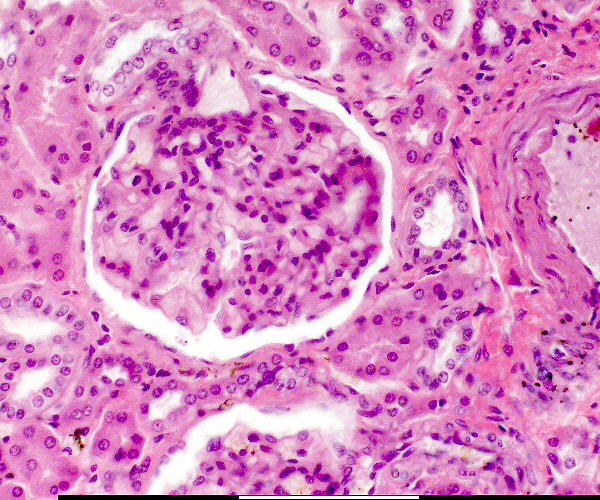

Bloedvat / Blood vessel Versamelbuis / Collecting tubule Makula densa / Macula densa Pariëtale selle / Parietal cells Pariëtale laag / Parietal layer Podosiete / Podocytes Urinêre spasie / Urinary space Vaskulêre pool / Vascular pole Visserale laag / Visceral layer Jukstaglomerulêre apparaat / Juxtaglomerular apparatus